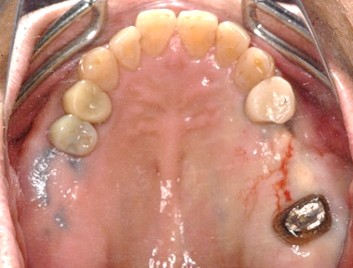

Before

冠の中で大きな虫歯になり支台の役割を果たしていませんでした。

【インプラント埋入前】

冠はブリッジを切断しただけで取れてきました。軟化象牙質を取り除いたところ、歯根しか残っていない状況で保存できるかどうかのぎりぎりのところでした。